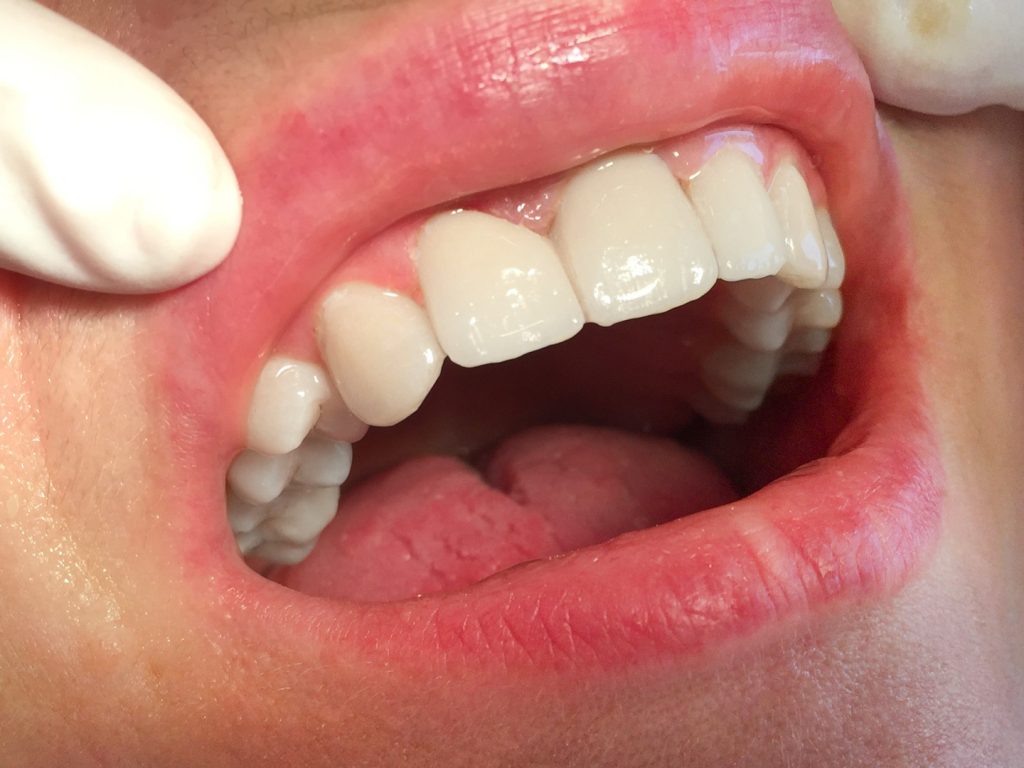

Megtörtént a saját fogaim előkészítése és a lenyomatvétel, majd néhány nap alatt a laborban elkészült a végleges fogpótlás; közben az ideiglenes pótlásnak köszönhetően egy órát sem töltöttem fog nélkül. Összességében a gyors, precíz és fájdalommentes beavatkozásnak hála egy hét leforgása alatt megszületett a csodálatos végeredmény – ahogy a főorvos úr fogalmazott –, az >>örök mosoly<<.

A végleges híd álomszép. A cirkónium természetes hatású és a főorvos úr elmondása szerint szilárd, tartós, strapabíró anyag, így a belőle készült pótlás a saját fog élményét adja!

De míg az önkéntelen mozdulatok egyre ritkulnak, a mosolyok mind gyakoribbak. Nem egy ember mondta már a környezetemből, hogy nahát, eddig nem is látták, hogy nekem ennyire szép fogaim vannak!

A családom szerint is csodás a végeredmény, és örömmel tölti el őket az, hogy jóval többet nevetek, mint annak idején.”

„Ezt én is megerősíthetem – kapcsolódik ezen a ponton a beszélgetésbe Anita párja, László. Anita új mosolya gyönyörű, ezt már büszkén mutogathatja és szerencsére mutogatja is! Felszabadultabb, vidámabb, fiatalosabb lett a beavatkozás hatására. Nőtt az önbizalma és elmúlt az a megfoghatatlan, de érezhető valami – nevezzük feszengésnek, bizonytalanságnak – ami korábban minden társas megnyilvánulására kihatott.